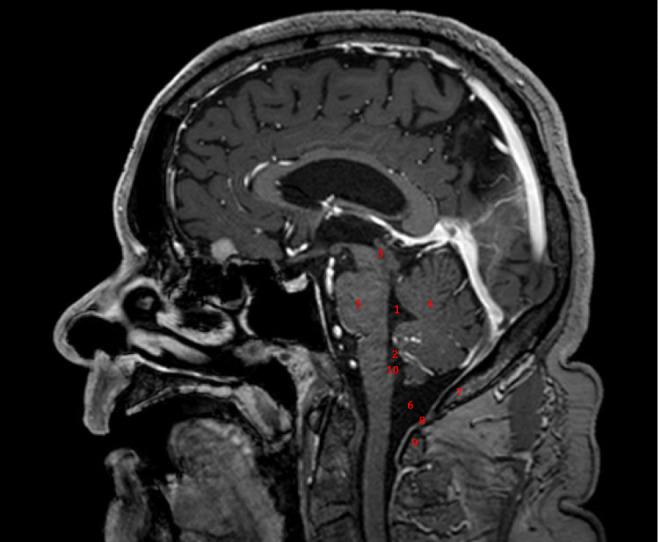

A 54-year-old female was referred to our clinic with a lesion of the lower fourth ventricle extending to the median aperture. Here, we report the use a minimally invasive sub-occipital approach (MISA) as a safe and effective surgical management.

We performed a MISA using a short midline incision and a 1-cm sub-occipital craniectomy. Dissection of the lesion was performed, and "en bloc" resection could be achieved. The lesion was confirmed to be a grade I sub-ependymoma.